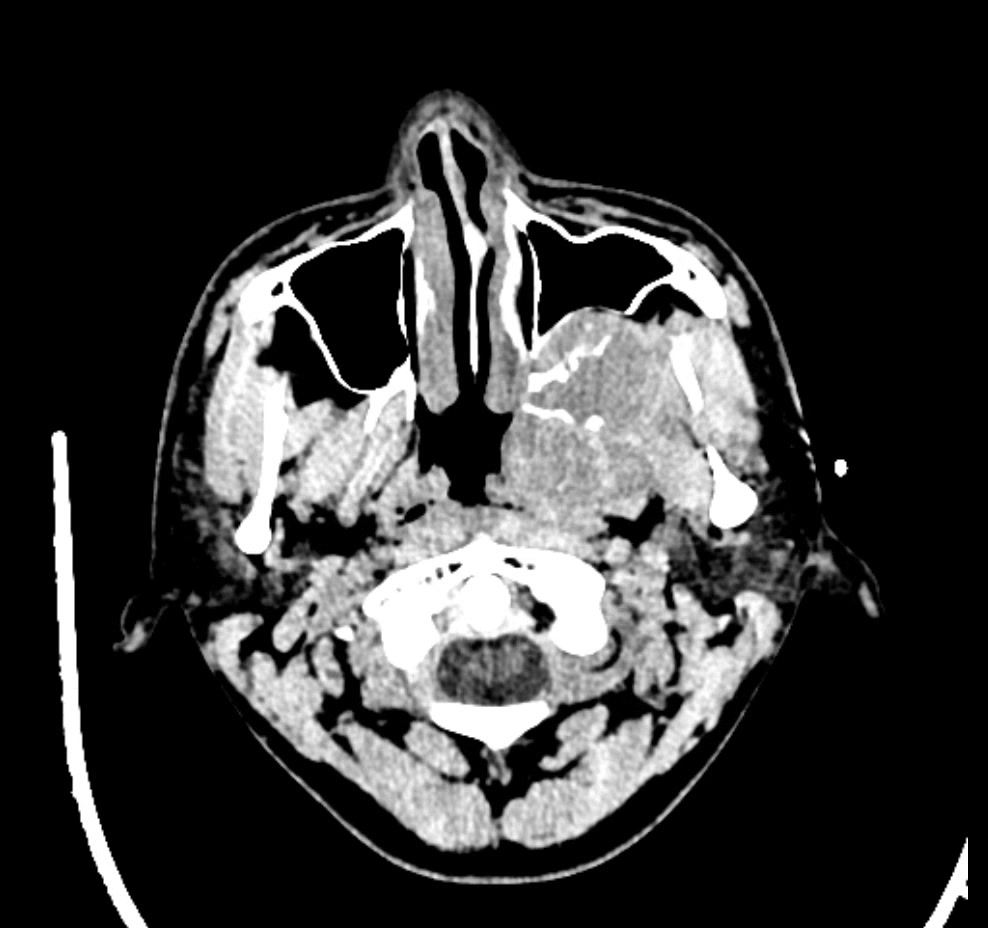

简要病史:左眼视力下降20余天,伴肿胀疼痛不适半月

CT增强: